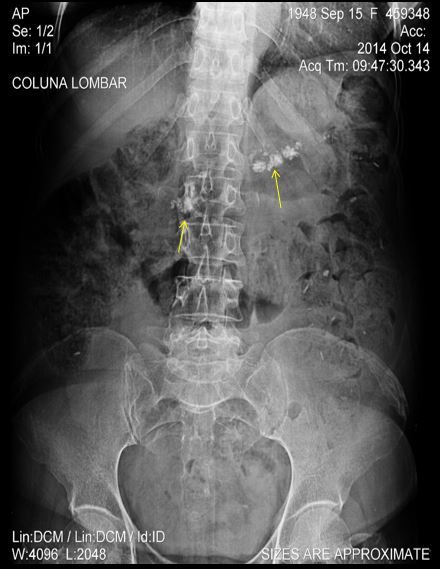

DOR LOMBAR BILATERAL, MAIS INTENSA

À DIREITA.

NOME DO EXAME?

NOME DA INCIDÊNCIA?

ACHADOS?

DIAGNÓSTICO?

RD SIMPLES DO ABDOME.

DECÚBITO DORSAL

IMAGEM CÁLCICA VOLUMOSA NO HIPOCÔNDRIO ESQUERDO MOLDANDO PELVE E CÁLICES. HÁ OUTRA IMAGEM CÁLCICA À DIREITA EM PROJEÇÃO URETERAL ( NÍVEL DE L3)

CÁLCULO CORALIFORME À ESQ E CÁLCULO URETERAL À DIREITA.

DOR LOMBAR, AP DA COLUNA LOMBAR, PEGANDO TODO ABDOME.

ACHADOS RADIOLÓGICOS? DIAGNÓSTICO?

HÁ IMAGENS CÁLCICAS ( SETAS AMARELAS )NA REGIÃO EPIGÁSTRICA EM PROJEÇÃO DO PÂNCREAS ( NIVEL DE L1 E L2)

PANCREATITE CRÔNICA

HÁ GASES, FEZES E RESÍDUOS MEDICAMENTOSOS (COMPRIMIDOS) NO CÓLON.